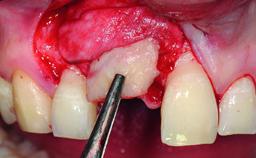

| Bone Augmentation | Horizontal|Simultaneous |

| Augmentation Materials | Xenogenous|Membrane |

| Soft Tissue Grafting | Simultaneous |